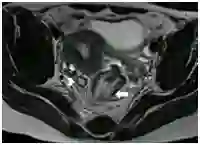

直肠系膜淋巴结和髂内淋巴结属于N分期,密度信号和淋巴结形态较大小能更好的预测淋巴结受累,表现为不规则边界和不均匀密度信号(图14),94%受累淋巴结只有5mm大小。推荐高分辨薄层T2加权像鉴别波尔卡圆点淋巴结征象,表现为正常大小转移淋巴结内部低密度信号(图14B),通常阳性淋巴结位于原发肿瘤水平或之上,与头端引流有关。精确评估淋巴结状态很重要,阳性是新辅助放化疗适应症,CRM 1mm内淋巴结必需报告,可能会影响CRM。直肠系膜外或侧方盆腔淋巴结,如髂外淋巴结、闭孔淋巴结和后腹膜淋巴结,为M疾病,进展期下位直肠癌上述淋巴结阳性更多。

图14  直肠淋巴结转移。A.轴位T2加权像显示直肠前壁肿物(箭头)和直肠系膜淋巴结(长箭头),淋巴结边缘不规则,密度信号不均匀;B. 波尔卡圆点淋巴结征象,轴位T2加权像显示6-12点半环周肿瘤(长箭头),小的直肠系膜淋巴结呈点状低信号,与波尔卡圆点相似(箭头);插入图像显示波尔卡圆点淋巴结。